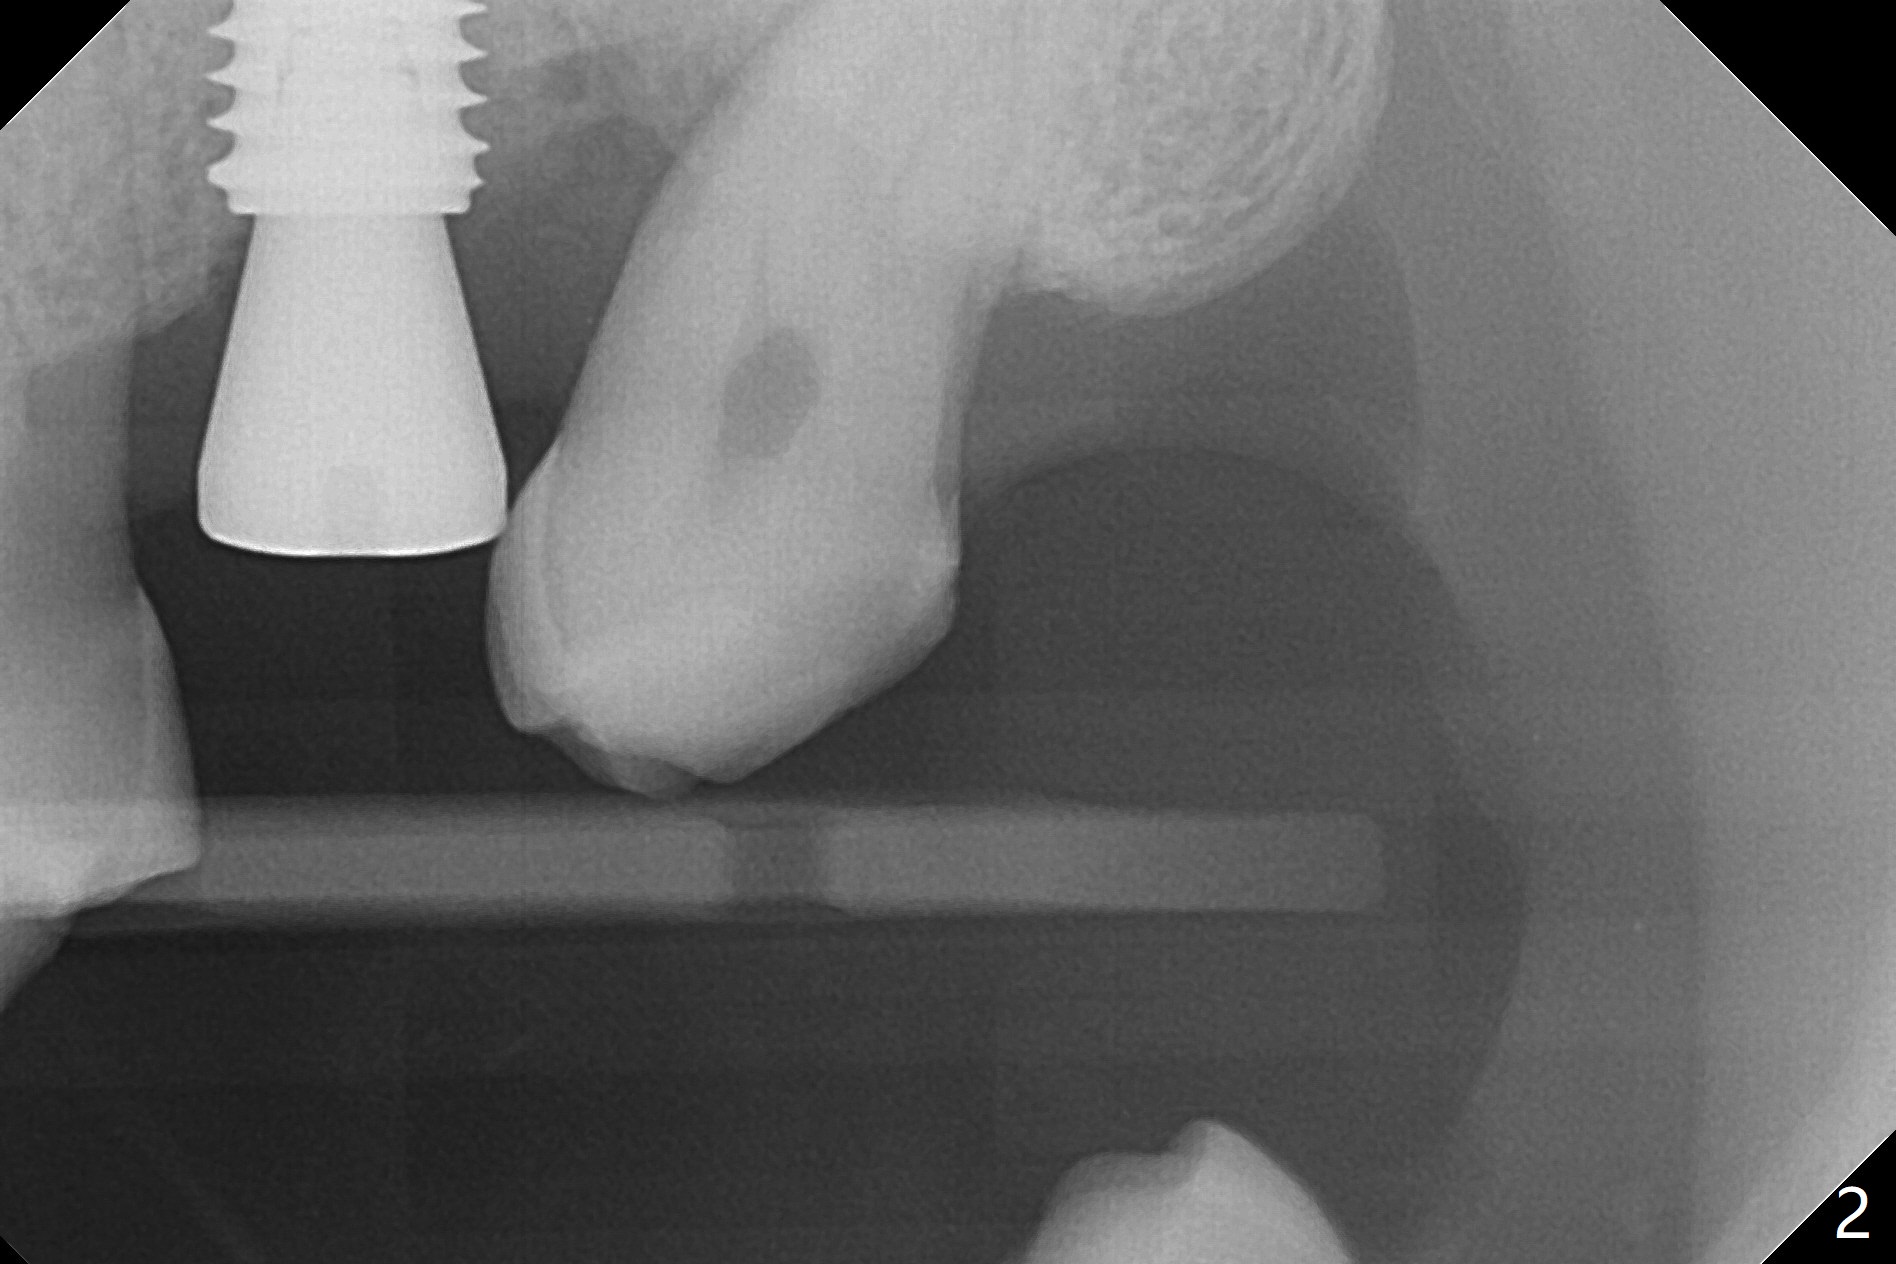

Osteotomy is conducted at #15 according to drill sequence (including the depth of the last drill (no tapping)), but the 5x10 mm implant is placed ~ 1mm shy of the planned depth (Fig.1 (red line: sinus floor)). Clinically the implant is ~ 2 and 4 mm subgingival buccal and palatal, respectively. Bitewing shows the implant being subcrestal mesial and equicrestal distal (Fig.2). If the implant has to be placed deeper, can a 4.0x13 mm drill be used?